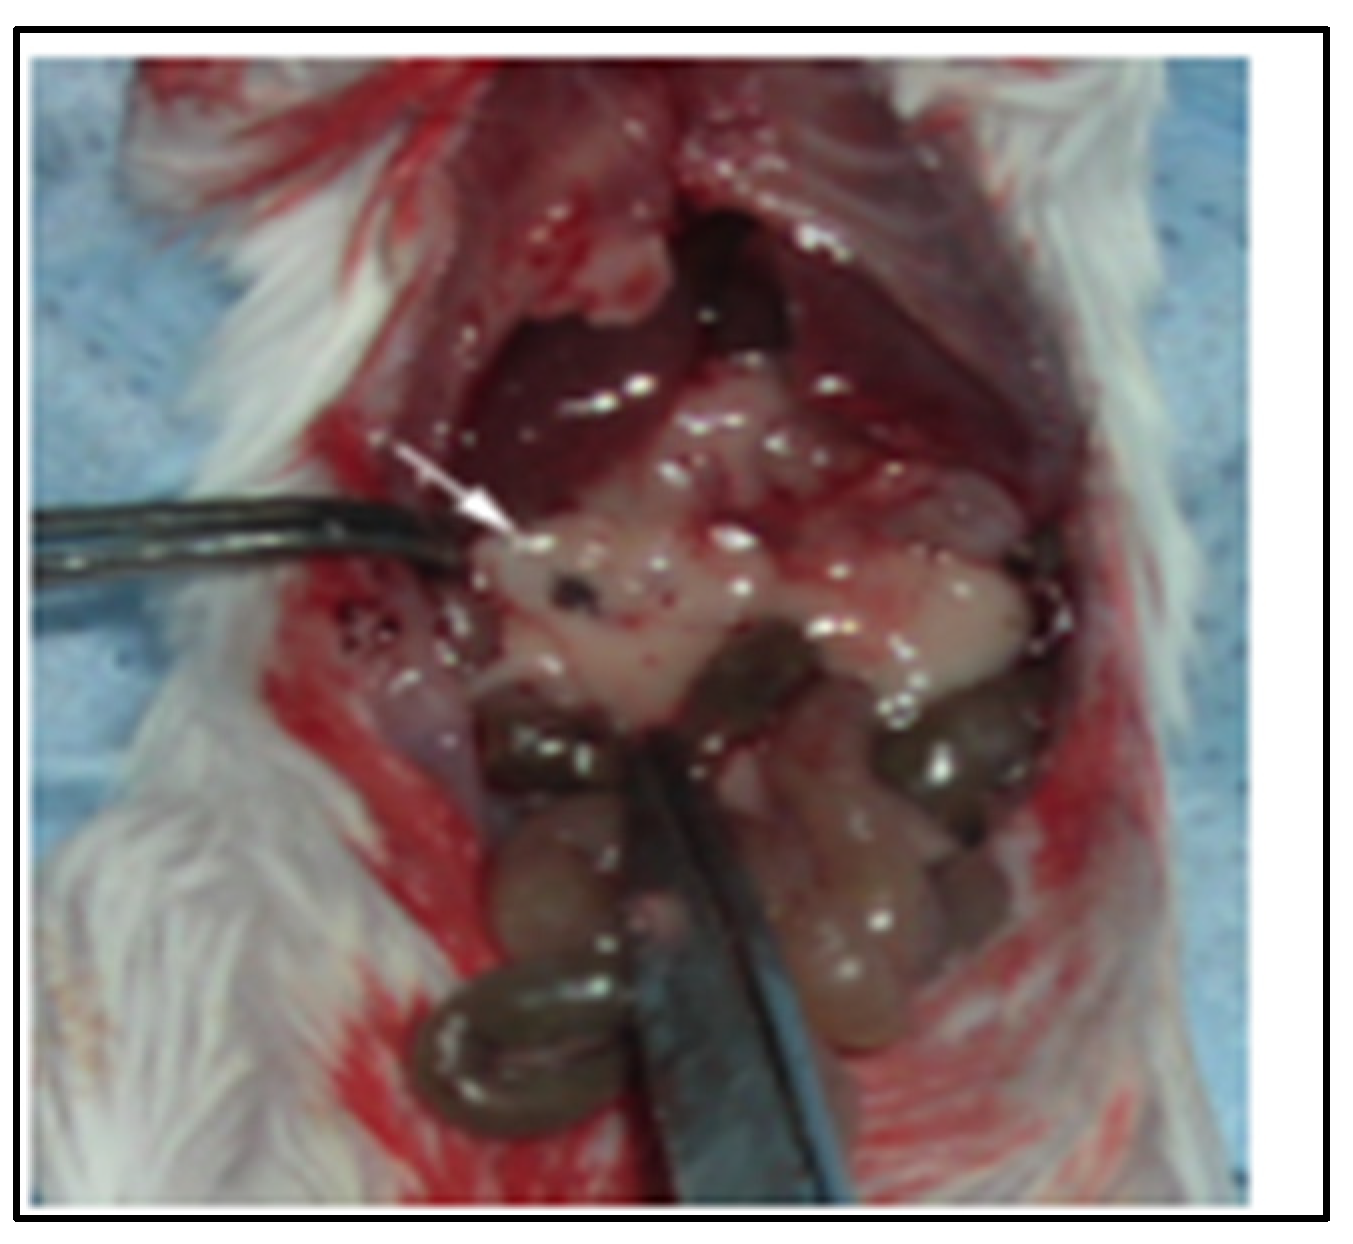

2.2. SV.IL-12 Can Reduce Metastasis in a Pan02 Syngeneic Mouse Model